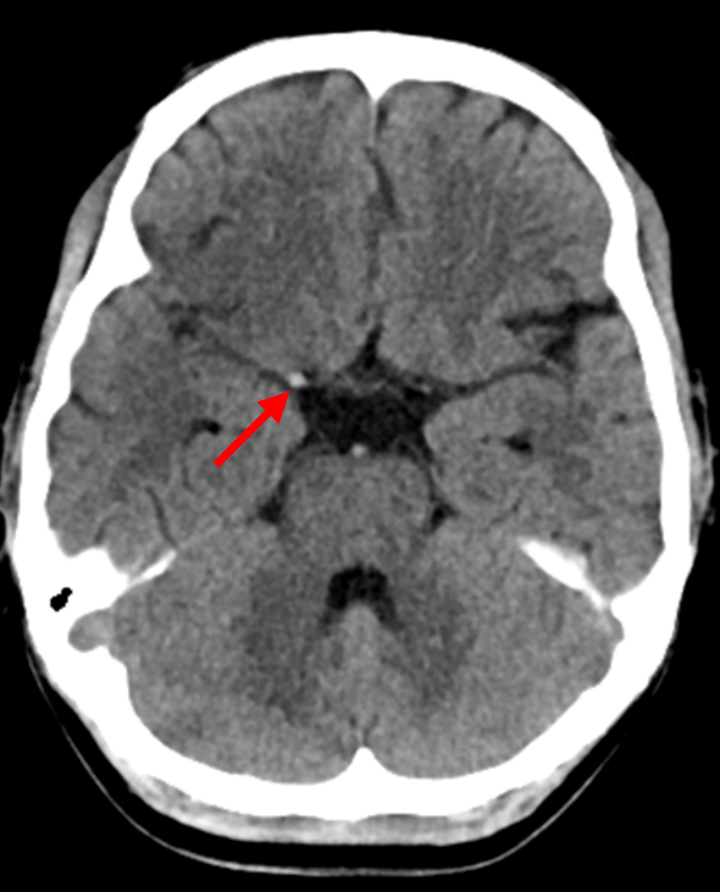

图1 图2

患者头颈部CTA(图1.右侧大脑中高密度影;图2.右侧颈内动脉末端、大脑中动脉闭塞)